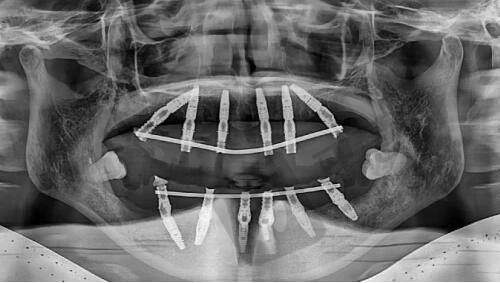

在异物取出方面,钟杰光医生运用SEER频谱智能清除术,其快速、直观的光谱数据图像获取技术可快速识别出注射物的位置、种类和分布情况。再配合异物取出光导设备与高清3D内镜,能更精细地定位生长因子增生物。针对不同注射时长和发展阶段的异物,他会进行逐层分析,多方位、多层次、多角度捕捉粉碎,确保异物取出干净。在馒化修复方面,他会进行个性化面诊,根据每位求美者的具体情况制定专属修复方案。采用微创技术进行修复,减少对正常组织的损伤,降低术后肿胀和瘀青的风险,缩短愈合期。同时,他追求自然的美感,通过精细的修复技术让面部线条更加流畅,比例更加协调。